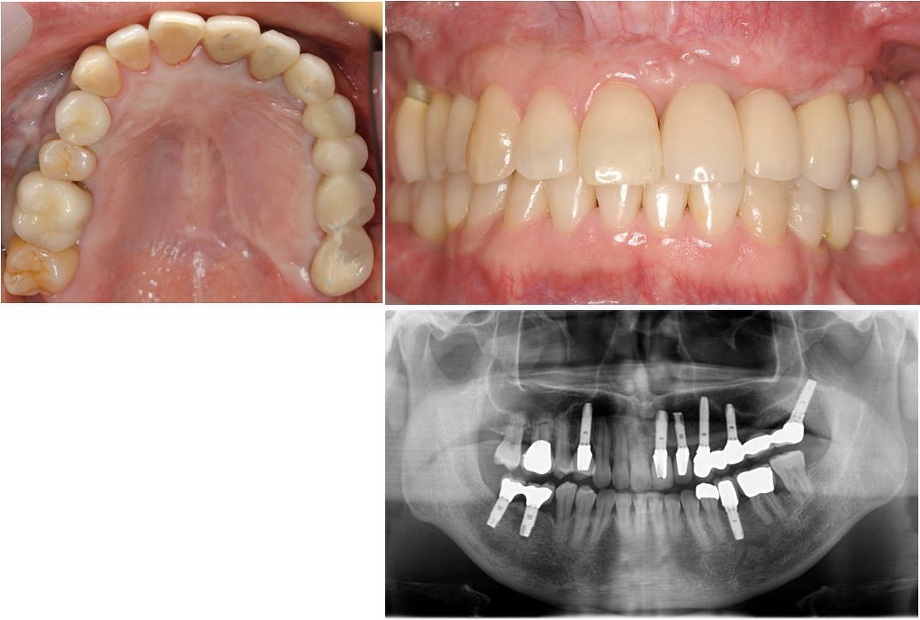

歯がなくなり、骨がやせてしまった場合は、骨を増やす処置をしてインプラント治療をしなければ下図のような審美的に良くない結果になります(他院で治療を受け、再治療を行うことになった患者さん)。

したがって、このようにならないように、やせた骨を回復させるために骨造成が必要となり、当院では、自家骨移植(ご自分の下顎骨の一部を移植します)、歯槽骨延長術(詳細は後述)を単独あるいは併用して、審美的に良好な結果を得ています。